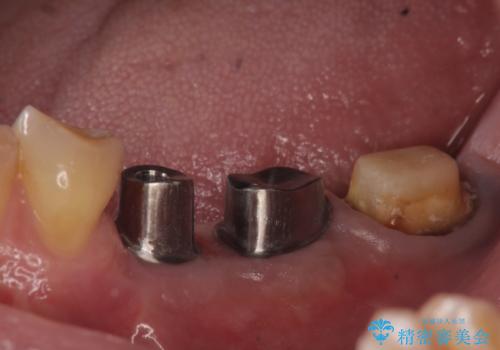

欠損部位である左下5、6番目にインプラントを埋入し、オールセラミッククラウンによる補綴を行いました。

ストローマンについて

当院では主にストローマンという種類のインプラントを治療に用いています。

ストローマンは世界的にもNo1のシェアを誇り、骨との適合にも優れたインプラントです。